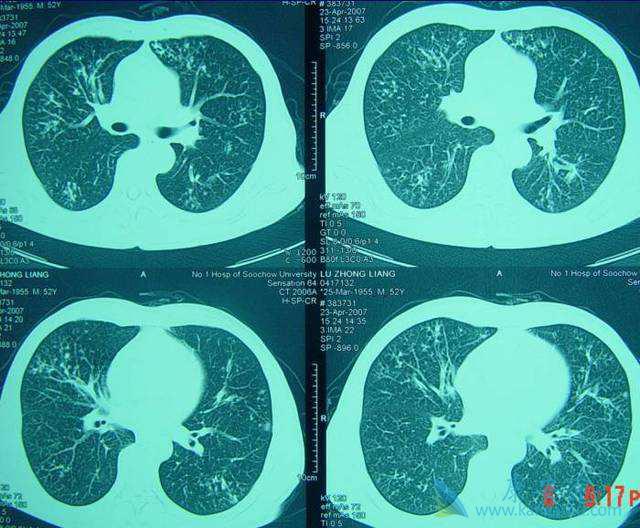

转移性肺癌的意思就是在患者体内的任何位置的恶性肿瘤都是通过各种方式转移到患者的肺部。大约有60%的恶性肿瘤在初次检查时就有肿瘤转移,其中30%~50%肿瘤转移到肺部。像不同的肿瘤转移到肺部的发生率不同,其中,甲状腺癌、乳腺癌、肾癌、绒毛膜癌、骨肉瘤发生率高可达60%以上。肺癌转移的发生率与原发肿瘤的生物学特性和机体的免疫功能状态有关。

除此之外,转移性肺癌的发生与肿瘤相关的信号和基因异常有关。而转移性肺癌大多为遍及两侧肺的多发性病灶,大小不一,密度均匀,对这些晚期癌肿病例,目前尚无有效的治疗方法。少数病例肺内只有单个孤立的转移病灶则可考虑外科治疗。外科手术治疗、化疗和放射治疗是转移性肺癌的三个主要治疗方法。治疗的选择需要视原发肿瘤的状态、转移性肺癌的类型、部位、数量及患者的一般状况来决定。外科手术治疗是转移性肺癌治疗的第一选择,也是目前治疗转移性肺癌的标准治疗手段。如果没有其他部位的转移,肺转移瘤切除术可以达到根治的效果。许多肿瘤对于化学治疗(化疗)和放射治疗(放疗)均不敏感,如软组织肉瘤肺转移,手术是重要的治疗手段。从经济学的角度,手术的成本、效果比值也更高。不过,终的选择都要看医生的指导。